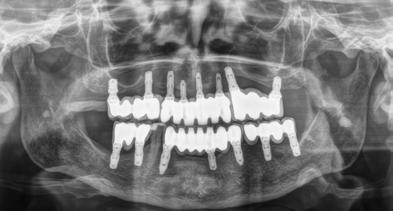

Fueron reclutados 8 pacientes en los que se insertaron 13 implantes que cumplieron con los criterios de inclusión previamente establecidos. De ellos, 3 fueron hombres y 5 mujeres con una edad media de 74.8 años (+/- 13.7). Ningún paciente era fumador y como patologías sistémicas asociadas, 2 pacientes refirieron hipertensión en tratamiento farmacológico. La posición dental más frecuentemente restaurada fue para la zona de 14, 34, 35 y 45 con un 15.4% para cada una de ellas. El resto de posiciones: 15, 24, 25, 44 y 46 tuvieron una frecuencia de 7.7%. La longitud de los implantes estudiados fue de 6.5 mm en el 69.2% de los casos y de 5.5 en el 30.8% restante. El diámetro de los implantes osciló entre 2.5 mm (23.1%), 3 mm (30.8%) y 3.3 mm (46.2%), presentando todos ellos una plataforma de

3 mm. La distribución del diámetro, longitud y posiciones de los implantes estudiados se muestran en la Figura 1

La densitometría media de la zona donde se insertaron los implantes fue de 673 Hu (+/- 274.3), siendo el torque medio de inserción para todos los implantes incluidos en el estudio de 3.9 (+/-14.2). En 3 de los implantes insertados se empleó como técnica accesoria la sobrecorrección vestibular con hueso autólogo obtenido de fresado unido a PRGF-Endoret y en uno de los implantes elevación de seno transalveolar con hueso autólogo obtenido del fresado unido a PRGF-Endoret también como material de relleno. En 8 de los implantes (61.5%) se llevó a cabo carga inmediata, siendo carga diferida para el 38.5% restante. El tiempo medio de seguimiento fue de 15.3 meses (+/- 5.08) no encontrándose

eventos adversos en las prótesis ni en los implantes durante este tiempo siendo la supervivencia de los implantes estudiados del 100%.

Todos los implantes fueron rehabilitados mediante prótesis múltiples, formando parte de puentes de más de un implante, incluso de rehabilitaciones completas en 2 casos. Las prótesis en todos los casos fueron atornilladas sobre transepitelial

múltiple (Multi-im®). La media de la pérdida ósea mesial de todos los implantes fue de 0.24 mm (+/- 0.62) y la media de la pérdida ósea distal de 0.19 mm (+/- 0.59).

En las Figuras 2-27 se muestra uno de los casos incluidos en el estudio donde se situaron 4 de los implantes que forman parte de la muestra, por lo que hemos creído que era uno de los más representativos.